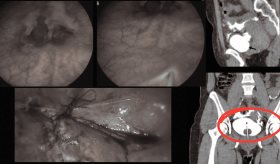

"Tenemos un caso en estudio que pronto se va a publicar: un cáncer testicular avanzado, muy raro, que nos llamó la atención por su tamaño. Eso nos hace pensar que, en algunos casos, los tumores se están presentando más grandes que antes", comentó, aclarando que aún no se trata de una tendencia confirmada, pero sí de un indicio que merece atención.

Por otra parte, el especialista advirtió que, en la práctica clínica, han comenzado a identificar casos más avanzados de lo esperado, en parte debido al temor que aún existe entre los pacientes para consultar a tiempo. La progresión de este tipo de tumores puede ser rápida, por lo que el diagnóstico temprano resulta crucial para lograr una curación efectiva.

"Hemos visto tumores más avanzados de lo que quisiéramos ver, y muchas veces es por el miedo. Una vez un joven nota alguna irregularidad, especialmente si siente el testículo duro, debe acudir de inmediato al urólogo. Estos tumores tienden a crecer rápidamente y días o semanas pueden marcar la diferencia en el estadio de la enfermedad", señaló.

Hoy en día, señaló, una de las herramientas diagnósticas clave es el sonograma testicular, un examen no invasivo que puede brindar claridad sobre cualquier anomalía y permitir actuar a tiempo. "Todo joven debe autoexaminarse, y si hay alguna duda, un sonograma testicular puede darnos luz sobre lo que está pasando. Es sencillo, accesible y puede salvar vidas", concluyó.